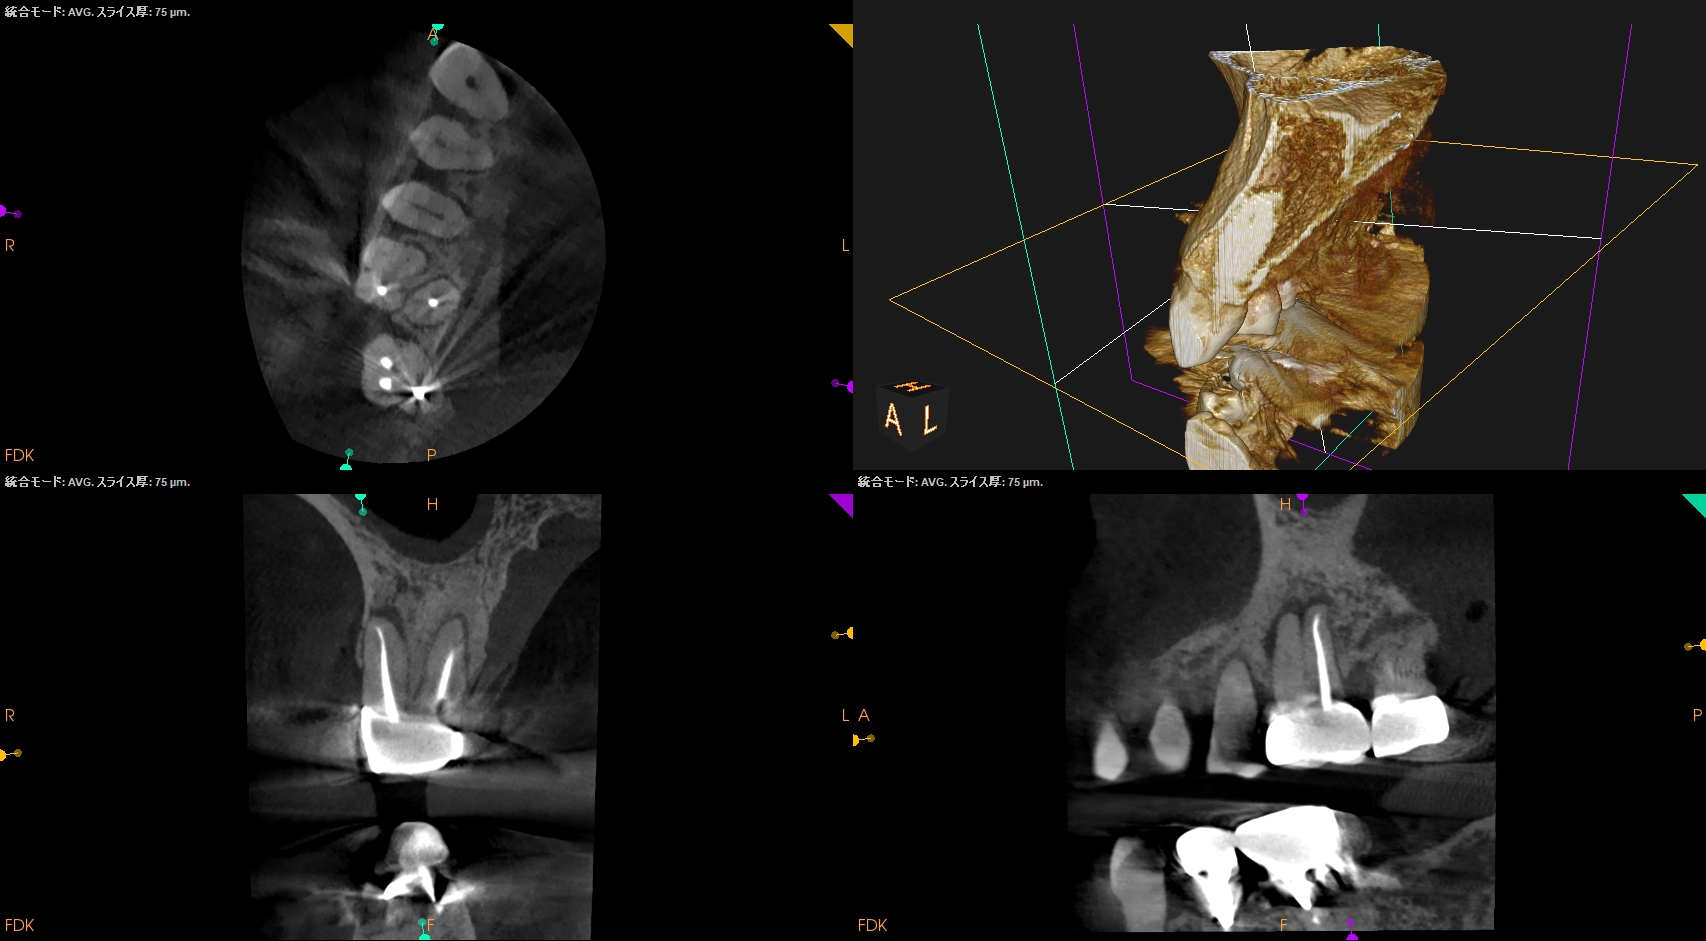

Pre-op CBCT(2024.11.25)

MB

DB

P

B

P根以外のMB,DBには根尖病変がありSinus tractがある。

ということは…

MB+DB Apicoectomyだ。